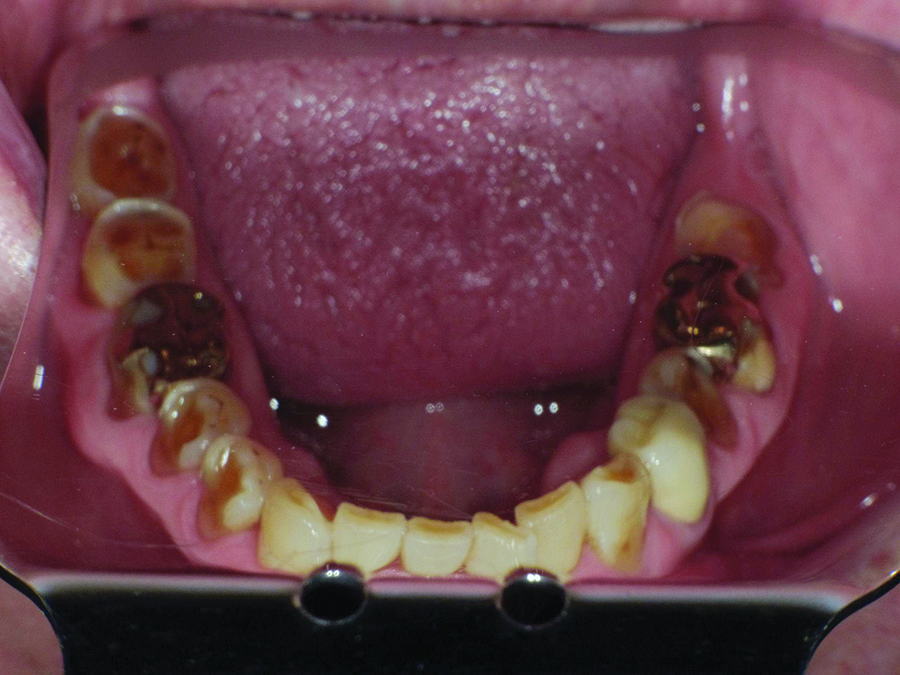

Severe buccal erosion, Nos. 28 and 29. Note shadow of pulp chambers.

Figure 4

Biomechanical: Significant tooth structure loss had occurred between 2009 and 2017 (Figure 1 through Figure 3). Severe attrition had occurred on the anterior teeth, especially tooth No. 11. Severe erosion and abrasion were present on teeth Nos. 11, 18, 20, 21, 28, 29, 31, and 32 (Fig-

ure 4). The patient had generalized sensitivity, and tooth No. 18 was painful due to deep erosion, which approached the pulp chamber. Teeth Nos. 7 and 10 had moved out of position and rotated (Figure 5). The progression of erosion over the 8-year period could also be seen radiographically and was especially noticeable on tooth

No. 18 (Figure 6 and Figure 7). The occlusal resins were lost on the mandibular molars, and the erosion and abrasion from the opposing crowns continued to erode the tooth structure.